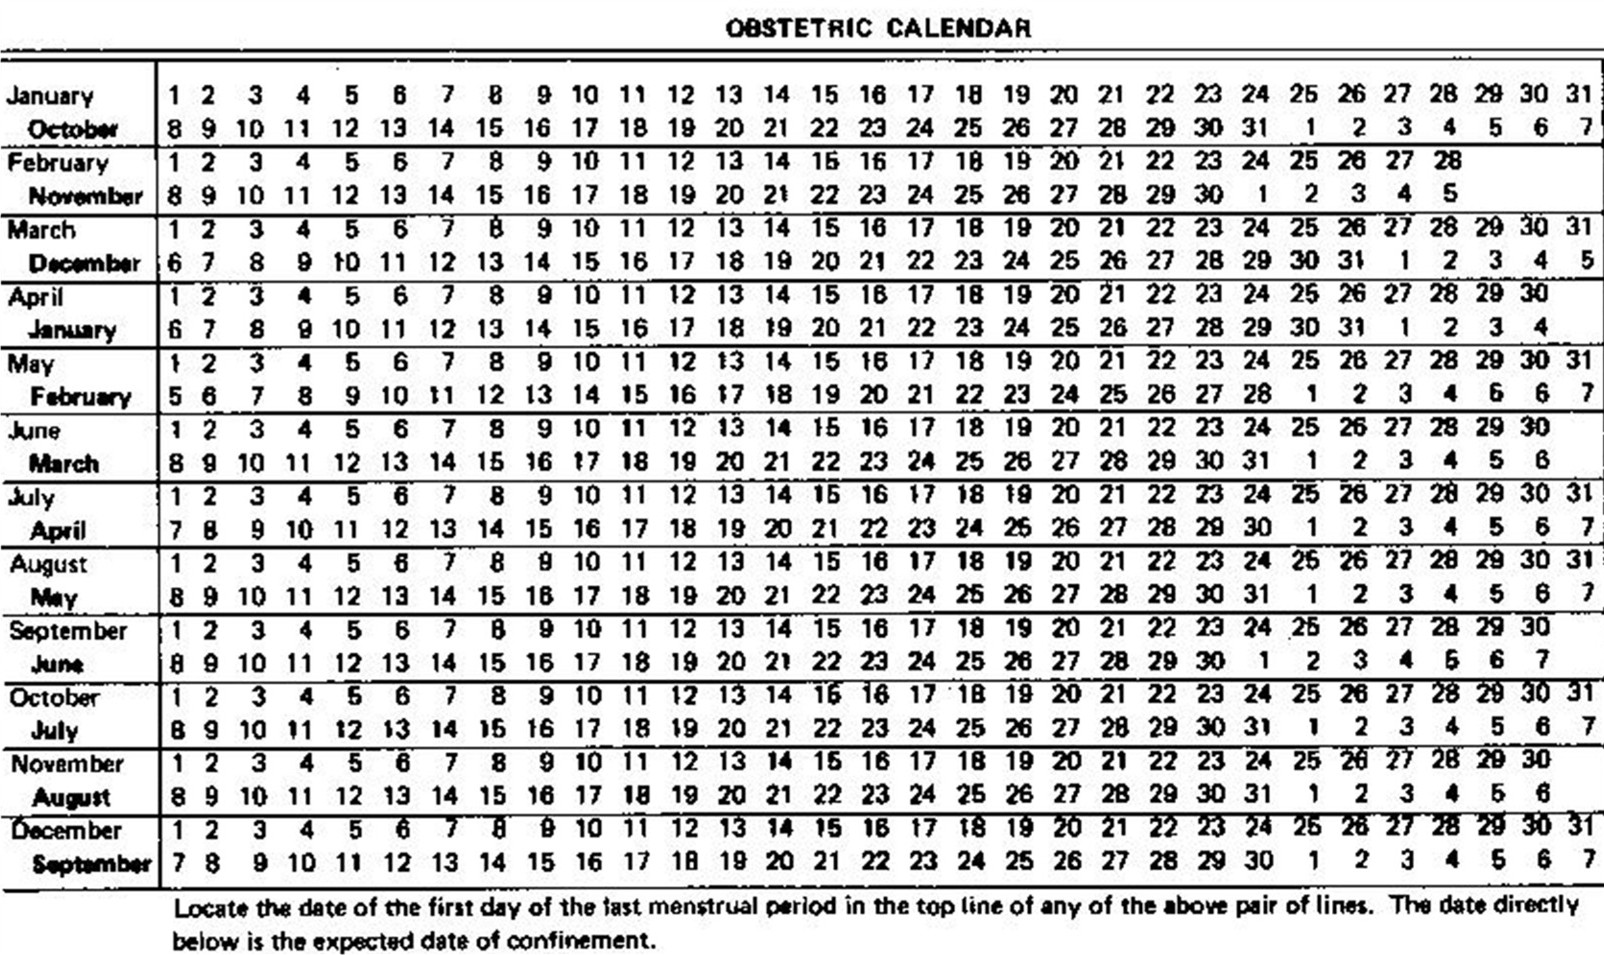

LEA, Livelli Essenziali di Assistenza, Curriculum Vitae, Padova, Vicenza, Venezia, Rovigo, Belluno, Verona, Treviso, Veneto, Harmony Test, ARIOSA, PrenatalSafe, Prenatal Safe, GENOMA, Vera Prenatal Test, Ecografia Tridimensionale, Ecografia Tridimensionale a Padova, Ecografia Tridimensionale a Vicenza, Test Combinato, Test Combinato a Padova, Test Combinato a Vicenza, Ultrascreen, Ultrascreen a Padova, Ultrascreen a Vicenza, Harmony Test, Harmony Test a Padova, Harmony Test a Vicenza, Ecografia 3D, Ecografia 3D a Padova, Ecografia 3D a Vicenza, Ecografia morfologica, Ecografia morfologica a Padova, Ecografia morfologica a Vicenza, Ecografia di I° livello, Ecografia di II° livello, Ecografia di 1° livello, Ecografia di 2° livello, Ecografia ostetrica, Ecografia ostetrica a Padova, Ecografia ostetrica a Vicenza, Ecografia in gravidanza, Ecografia in gravidanza a Padova, Bellitti Francesco Ginecologo, Ecografia in gravidanza a Vicenza, Ecografia 3 D, Ecografia 3 D a Padova, Ecografia 3 D a Vicenza, Ricerca DNA Fetale, Ricerca DNA Fetale a Padova, Ricerca DNA Fetale a Vicenza, Ecografia genetica, Ecografia genetica a Padova, Ecografia genetica Vicenza, Ecografista Accreditato, Ecografista Accreditato a Padova, Ecografista Accreditato a Vicenza, Ecografisti Accreditati, Ecografisti Accreditati a Padova, Ecografisti Accreditati a Vicenza, Bi-test, bi-test a Padova, bi-test a Vicenza, Osso nasale, osso nasale a Padova, osso nasale a Vicenza, Ostetricia, ostetricia Padova, ostetricia Vicenza, Ginecologia, ginecologia Padova, ginecologia Vicenza, Villocentesi, Villocentesi a Padova, Villocentesi a Vicenza, Amniocentesi, Amniocentesi a Padova, Amniocentesi a Vicenza, Ecografia ginecologica, Ecografia ginecologica a Padova, Ecografia ginecologica a Vicenza, Screening per la sindrome di Down, Screening per la sindrome di Down a Padova, Screening per la sindrome di Down a Vicenza, Test Harmony, Test Harmony a Padova, Test Harmony a Vicenza, Bitest, bitest a padova, bitest a Vicenza, Bi test, bi test a padova, bi test a Vicenza, 3D, 3D a Padova, 3D a Vicenza, 3 D, 3 D a Padova, 3 D a Vicenza, 4D, 4D a Padova, 4D a Vicenza, Ecografia 4D, Ecografia 4D a Padova, Ecografia 4D a Vicenza, 4 D, 4 D a padova, 4 D a Vicenza, Ecografia 4 D, Ecografia 4 D a Padova, Ecografia 4 D a Vicenza, Padova, Vicenza, Venezia, Rovigo, Belluno, Verona, Treviso, Veneto È opinione diffusa che basta fare una ecografia nel 5º mese di gravidanza, la cosiddetta ecografia “morfologica”, per essere certi che nascerà un bambino “sano”, ma formulare la prognosi di una gravidanza e del relativo parto ed esito neonatale rimane la più grande sfida della medicina materno-fetale. Le patologie fetali sommariamente possono essere distinte in 5 gruppi: malformazioni, malattie geniche, anomalie cromosomiche, infezioni fetali, danno cerebrale ipossico. Le Malformazioni sono difetti anatomici di un organo o di un sistema di organi che derivano da un’alterato sviluppo dell’organo fetale durante la morfogenesi. Nella maggior parte dei casi non è possibile risalire alla causa dell'anomalia; in altri casi, invece, la causa della malformazione è riconducibile ad anomalie cromosomiche, malattie geniche, assunzione di farmaci, infezioni fetali, malattie materne, etc. Tali condizioni possono indurre Teratogenesi (malformazioni per esposizione durante l’organogenesi) o Mutagenesi (mosaicismo somatico localizzato che può esprimersi nella vita futura o nelle generazioni successive). Un feto ogni 40 è affetto da una malformazione. Fra le malformazioni più frequenti vi sono: il labbro leporino, l’idrocefalia, la spina bifida, l'atresia esofagea, l’ernia diaframmatica, la gastroschisi, l'onfalocele, etc. Purtroppo la diagnosi prenatale delle malformazioni è molto difficile e in alcuni casi impossibile; pertanto talvolta è tardiva (IIIº trimestre di gestazione) o non viene fatta. Le Anomalie Cromosomiche sono alterazioni del numero (aneuploidie) o della struttura (anomalie strutturali) dei cromosomi. Il corredo cromosomico umano è costituito da 46 cromosomi (23 coppie): 44 autosomi e 2 gonosomi (cromosomi sessuali), 23 di origine paterna e 23 di origine materna. Le anomalie riguardanti il numero sono le monosomie, le triploidie, e le poliploidie, mentre quelle riguardanti la struttura sono le delezioni, le traslocazioni e le inversioni. Le anomalie possono essere in linea pura, cioè presenti in tutte le cellule dell’individuo o in mosaico, cioè solo in una certa percentuale di cellule. Le trisomie, nelle quali è presente un cromosoma soprannumerario non sono trasmesse ereditariamente, ma insorgono casualmente a causa della non disgiunzione cromosomica, spesso legata all’età materna. Le anomalie strutturali, quali delezioni e traslocazioni, sono molto più rare, ma possono essere trasmesse da uno dei genitori che ne sia portatore. Circa un feto ogni 100 ha una anomalia cromosomica grave. In linea di massima le anomalie cromosomiche possono determinare danni a livello fisico, mentale e psico-motorio. Fra le anomalie cromosomiche vi sono la Trisomia 21 (o Sindrome di Down), la Trisomia 18 (o Sindrome di Edwards), la Trisomia 13 (o Sindrome di Patau), la Monosomia X (o Sindrome di Turner), la Sindrome di Klinefelter, etc. Purtroppo per moltissime anomalie cromosomiche la diagnosi prenatale non fornisce un’indicazione sicura al 100%, ma la risposta può essere espressa sotto forma di probabilità percentuale o riferita a casi analoghi riportati dalla letteratura medica. Spesso la stessa anomalia può provocare problematiche più o meno gravi ed avere effetti molto diversi da un individuo all’altro, cosicchè la prognosi risulta molto difficile. Le Malattie Geniche sono causate dall’alterazione di una base azotata su 3.000.000.000 di sequenze di basi azotate che formano i circa 100.000 geni che costituiscono il DNA di cui sono composti i cromosomi. Le malattie geniche conosciute sono oltre 7000; attualmente, però, solo una parte di queste (circa 300) sono diagnosticabili in epoca prenatale e solo in alcuni laboratori di genetica e diagnosi molecolare, e non vengono ricercate con le villocentesi o le amniocentesi di routine. Per ricercare le malattie geniche nel DNA fetale è necessaria una specifica e preventiva richiesta al genetista (es. se i genitori sono portatori di una malattia genica conosciuta). Circa il 3% dei nati ha una malattia genica. A seconda dell’estrinsecazione della malattia, le malattie geniche sono suddivise in malattie autosomiche recessive, autosomiche dominanti o legate al cromosoma X (X-linked). Fra le Malattie geniche ci sono la Fibrosi cistica, la Talassemia, l’Anemia falciforme, la Sindrome Adrenogenitale, l’Osteogenesi imperfetta tipo Iº, la Sindrome di Marfan, la Distrofia Miotonica, la Chorea di Huntington, la Distrofia muscolare di Duchenne, l’Emofilia, la Sindrome dell’X Fragile, etc. Alcune anomalie possono presentarsi in forma più o meno grave, oppure avere un’età di esordio variabile, ma non è possibile prevedere né l’età di esordio né se il nascituro svilupperà la malattia in forma lieve o grave. L’ecografia è una tecnica che utilizza ultrasuoni (onde sonore ad alta frequenza), che in parte attraversano i tessuti ed in parte vengono riflessi (eco) e trasformati in immagini nel monitor dell’ecografo, consentendo di osservare il feto dentro l’utero; con le procedure oggi adottate, l’uso diagnostico dell’ecografia è ritenuto esente da rischi sia per la madre che per il feto. L’Ecografia fetale consente sia una valutazione morfologica e biometrica del feto (diagnosi delle malformazioni e valutazione della crescita), sia una valutazione dello stato di benessere fetale e della riserva funzionale. Sono stati riportati, inoltre, alcuni reperti ecografici potenzialmente utili per “sospettare ecograficamente” feti affetti da anomalie cromosomiche (come la Sindrome di Down o Trisomia 21, causata da un cromosoma 21 sovrannumerario trasmesso all'embrione dalla madre): due di queste tipiche stigmate predittive per anomalie cromosomiche sono l'assenza dell'Osso Nasale (non visualizzabile nel 60-70% dei feti affetti dalla Sindrome di Down) e l'aumentato spessore della Translucenza Nucale (cioè lo spessore cutaneo nucale). La possibilità di rilevare un'anomalia maggiore dipende dalla sua dimensione, dall'epoca di gravidanza, dalla posizione del feto, dalla quantità di liquido amniotico, dallo spessore della parete addominale materna; perciò e per i limiti intrinseci della metodica, è possibile che alcune anomalie, anche importanti, non siano rilevate. In alcuni casi può essere necessario eseguire l’esame con la sonda ecografica endovaginale, inoltre, può essere necessario ripetere l'esame più volte o sottoporsi ad approfondimenti diagnostici specifici e mirati. Un reperto di “normalità” non esclude la possibilità che il bambino presenti una malformazione o una anomalia cromosomica (falso negativo), così come un reperto “anomalo” può essere rinvenuto in un feto sano (falso positivo). Un reperto di “normalità” non esclude la possibilità che il bambino presenti ritardo mentale, cecità, sordità ed altri difetti sensoriali e/o motori. Le anomalie congenite sono presenti nel 2.5-3% delle gravidanze (circa un feto su 40), in particolare le anomalie cromosomiche sono presenti nell’1% circa delle gravidanze. L’ecografia “morfologica” (consigliata alla 19ª-21ª settimana gestazionale) permette di escludere la maggior parte delle malformazioni maggiori, mentre altre anomalie, anche importanti, a causa delle ridotte dimensioni o delle modalità di evoluzione, è possibile che siano evidenziate tardivamente o non siano rilevate (alcune malformazioni cardiache, del sistema nervoso centrale, del tubo digerente, del sistema urinario, emorragie, cisti, tumori, etc.). Non è compito dell’ecografia la rilevazione delle cosiddette anomalie minori. Con l'ecografia non è possibile diagnosticare le anomalie genetiche, sia geniche (fibrosi cistica, talassemia, etc.), sia cromosomiche (come la Sindrome di Down). Un esame ecografico routinario (Iº livello) consente di identificare dal 30% al 70% delle malformazioni fetali maggiori, mentre una ecografia eseguita da un operatore particolarmente esperto (IIº livello) può incrementare il tasso di diagnosi fino al 90%. Le ecografie fatte nel corso della gravidanza sono complementari e sono ognuna un completamento della precedente, pertanto la difficoltà di escludere le anomalie fetali diventa ancora maggiore se il medico effettua una sola ecografia in tutta la gravidanza, in quanto la morfogenesi fetale è un evento evolutivo che non può essere colto in maniera omnicomprensiva con un unico esame ecografico. Non è un obiettivo dell’ecografia del secondo trimestre lo screening delle anomalie cromosomiche mediante la ricerca dei marcatori ecografici di cromosomopatia. Nel caso in cui venga riscontrata una anomalia fetale si consiglia di eseguire una ecografia presso un Centro di IIº livello e, in alcuni casi, lo studio del cariotipo fetale (mappa cromosomica), per accertare o escludere la presenza di anomalie cromosomiche, mediante Villocentesi, Amniocentesi. La legge 194/1978, che regolamenta l’interruzione volontaria della gravidanza, consente di interrompere la gravidanza entro il 180º giorno dal suo inizio (aborto terapeutico). Purtroppo la “vitalità” è difficile da definire a priori, quindi, in una percentuale limitata, ma non irrilevante, di casi il feto, una volta espulso, potrebbe sopravvivere, in quanto la sopravvivenza è possibile anche entro il 180º giorno. Il Profilo Biofisico Fetale Ecografico è un metodo per la valutazione del benessere fetale basato sulla sorveglianza di 4 variabili biofisiche fetali: movimenti corporei. movimenti respiratori, tono muscolare e quantità di liquido amniotico. Le prime 3 variabili sono regolate da centri nervosi, pertanto riflettono lo stato del Sistema Nervoso Centrale, mentre la quantità di liquido amniotico riflette la riserva funzionale del feto e fornisce, indirettamente, una al stima del compenso emodinamico. La Velocimetria Doppler è una metodica ecografica per mezzo della quale è possibile misurare la velocità del sangue nei vasi sanguigni della circolazione materna e feto-placentare e rilevare le variazioni di flusso tipiche della sofferenza fetale, che talvolta precedono di qualche settimana i segni biofisici della sofferenza stessa. Sia il Profilo Biofisico Fetale che la Velocimetria Doppler permettono, talvolta, la diagnosi precoce della sofferenza fetale quando, grazie ai meccanismi omeostatici del feto, non è ancora avvenuto il danno neurologico; ciò è importante per attuare una corretta condotta ostetrica al fine di prevenire il danno cerebrale feto-neonatale e ridurre l’incidenza di handicaps. Una delle più comuni cause di handicap è la sindrome di Down, causata da un cromosoma 21 sovrannumerario trasmesso all'embrione dalla madre (Trisomia 21). La possibilità di procreare un figlio affetto dalla sindrome di Down, seppur in percentuale diversa, è presente per le donne di tutte le età (vedi tabella).